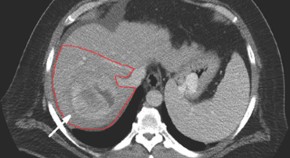

• This article considers the case of a 58-year-old man with a history of type II diabetes, obesity and hypertension who presented with non-alcoholic steatohepatitis-related liver cirrhosis and hepatocellular carcinoma (HCC), and self-referred for a second opinion. He was diagnosed with unresectable HCC. The patient underwent radioembolization with Yttrium-90 glass microspheres, which substantially decreased the tumor mass. 1 year after initial diagnosis with HCC the patient underwent orthotopic liver transplantation (OLT). He remains negative for recurrence of HCC 2.5 years post-OLT.

• Laura E. Moreno Luna

• Paul Y. Kwo

• Vijay Laxmi Misra